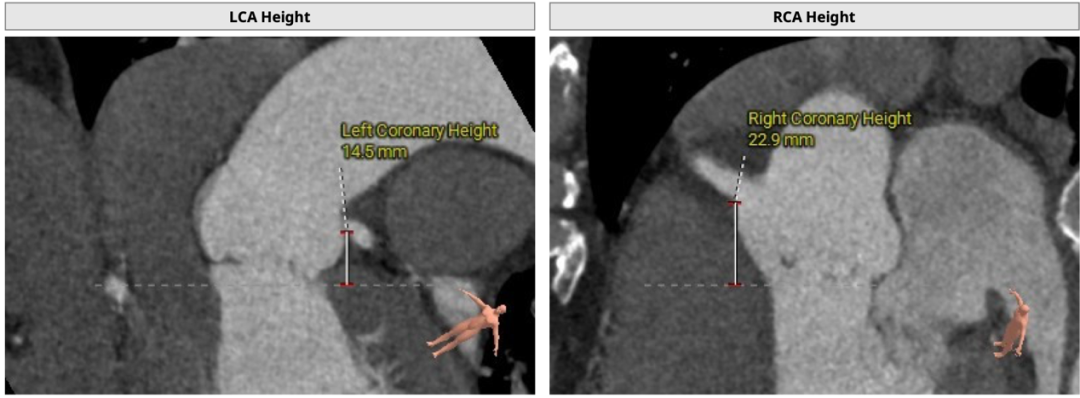

术中建议造影角度RAO:12°,CAU:30°:

心室角度55度: